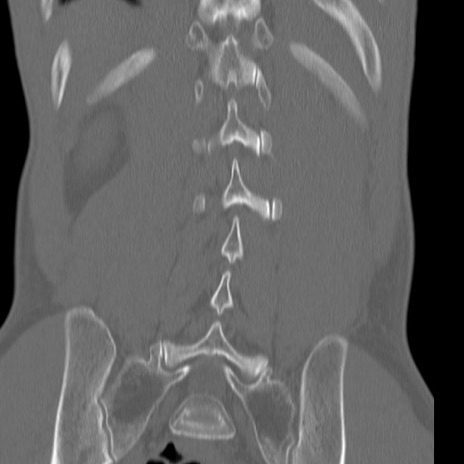

症例3 腰椎CT(冠状断像)

【症例】30歳代男性

【主訴】腰痛

【現病歴】本日旅行先で観光中に、友人と衝突し転倒し受傷。

【身体所見】麻痺なし、右下腿内側前面外側、左下腿内側に知覚鈍麻・しびれ

腰椎CT